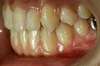

Intra Orale Gauche